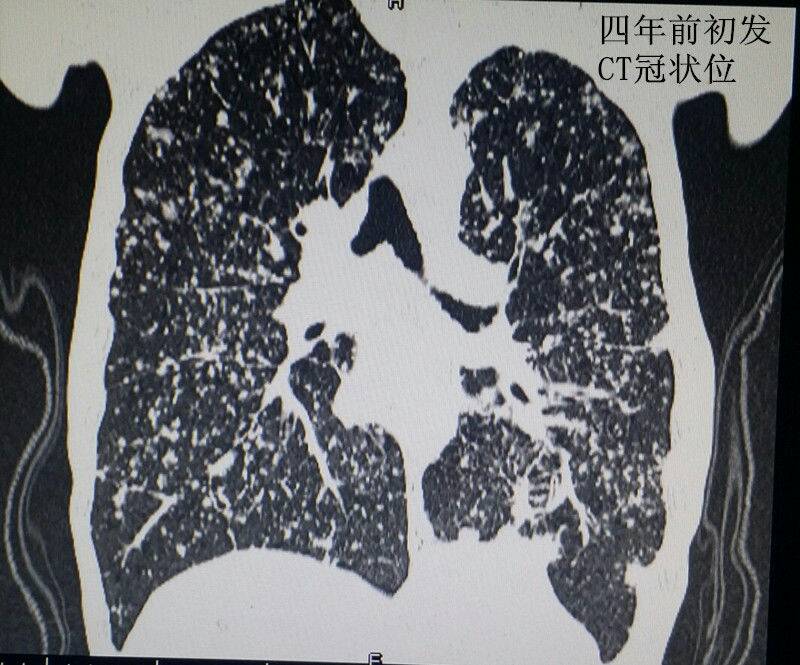

男性青年,未婚。 主诉:咳嗽数月,发现血尿三天。 现病史:患者半年前出现咳嗽症状,自服“消炎药”可减轻,一直未愈,近来加重。右腰背部偶感不适。发现终末血尿三天。患者自述近来消瘦、乏力。精神可,饮食可,睡眠好。 既往史:患者四年前因粟粒性肺结核就诊于当地结核病医院,给予口服抗结核治药物治疗(具体药物不详),后复查未见明显异常。 个人史:吸烟十年。 婚育史:未婚。 家族史:父母体健,无遗传病史。 实验室检查:肌酐:200umol/L(59-104) 尿素:10.4umol/L(2.86-8.2) 本院非结核病防治医院,无结核相关实验室检查。其余检查无阳性发现。 影像学检查(见插图): 1.四年前胸部平片及CT显示:双肺密布粟粒样结节,考虑肺结核。 2.现在胸部CT示:右肺尖及双肺背侧可见片状不规则高密度影,右肺中叶见厚壁空洞。考虑空洞型肺结核。 3.现在行腹部立位平片及CT示:右肾呈高密度团块状,结合病史考虑肾自截。 4.为进一步明确分肾功能,行核素肾动态显像示:右肾未见明显血流灌注,右肾未见明显显影,右肾功能重度受损,右肾肾图呈低水平延长线性改变。左肾功能大致正常。 诊疗经过:鉴于右肾无功能,行右肾摘除术(送病理,回报:肾结核)。请胸外科会诊,建议转入胸外科行肺段切除术。目前右肾摘除术后。 小结:近年来结核病例有上升趋势,尤其是肺结核。本病例类似的情况较少见,特此分享供大家学习。